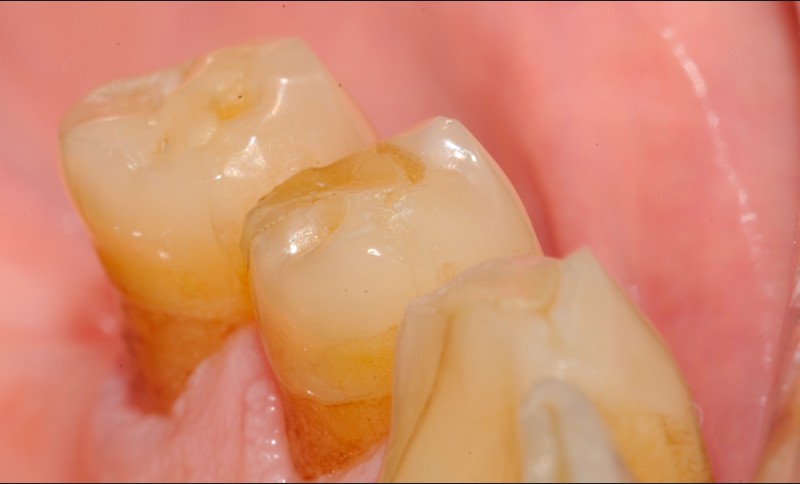

Aspect clinique et radiographique des lésions d’abrasion

Cliniquement, les lésions d’abrasion sont caractérisées par des facettes lisses, une absence de convexité et des bords à angles vifs. La flexibilité du ligament alvéolo-dentaire va entrainer un frottement au niveau des points de contact, qui peuvent se transformer en surfaces de contact (fig. 2c-d, 3 et 4b-c).

Radiographiquement, on observe une perte des cuspides et un aspect plan des faces occlusales (fig. 2a-b et 4a).